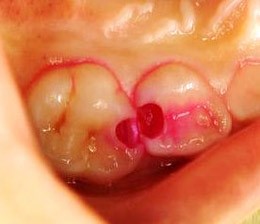

虫歯検知薬は、虫歯部位を赤く染め出してくれる薬液です。一目で虫歯とそうでない部分が分かるため、着色した部分だけを除去することで、歯の削り過ぎを回避します。

歯科治療は狭く暗いお口の中を診るため精密さが要求されますが、特にお子さんの歯は小さいため、肉眼だけで確認できる範囲には限界があります。

そこで肉眼の何倍も視野を拡大してくれる高倍率ルーペを使用し、治療部位の見える化を徹底しています。